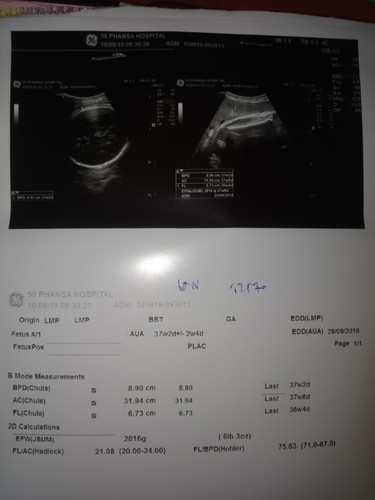

หมออีกคนบอกว่าได้34+6วีคเเต่วันนี้พบหมออีกคนซาวดูเเล้วบอกว่าได้37+2วีคเเล้วตกลงยังไงค่ะดูให้หน่อยค่ะ

ในใบซาวด์เป็น 37+2 ค่ะ